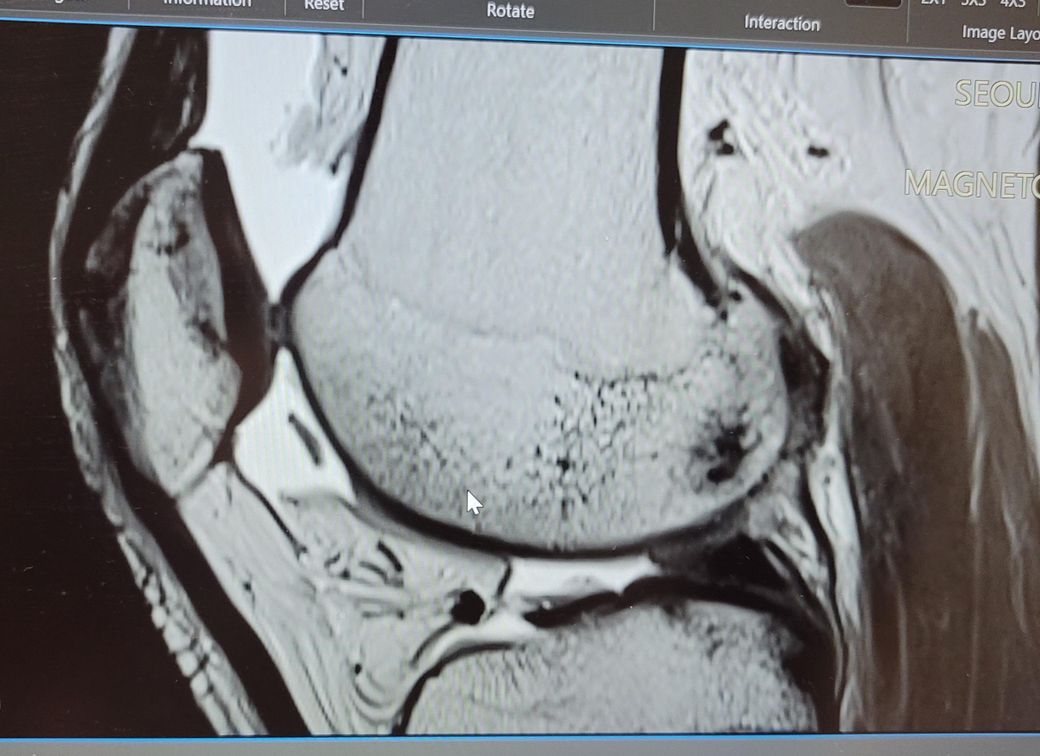

무릎 관절 유리체 제거 꼭 해야하나요?

활차구 연골이 떨어지면서 유리체가 생겼습니다.

현재는 물이 차 있는 상태이긴한데

무릎 펴고 할 때 통증은 없습니다

• 1번 째 사진